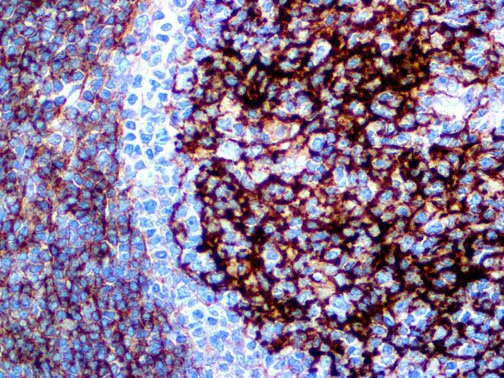

It is the ICU physician who is most likely to witness one of the deadliest manifestations of the abnormal immunological response, the cytokine storm syndrome (CSS). This response is also referred to by some as the cytokine release syndrome (CRS). CSS is characterized by continuous activation and expansion of macrophage and lymphocyte populations, which secrete large amounts of cytokines, causing the cytokine storm. This massive cytokine release is akin to hemophagocytic lymphohistiocytosis (HLH) disease, a syndrome characterized by initial unchecked and persistent activation of cytotoxic T lymphocytes and NK cells.

Clinical and laboratory manifestations of HLH include fever, enlarged liver and/or spleen, neurologic dysfunction, coagulopathy, liver dysfunction, cytopenias (i.e., low levels of erythrocytes, leukocytes, and/or platelets), hypertriglyceridemia, hyperferritinemia, hemophagocytosis, and eventually diminished NK cell activity as the immune system becomes progressively paralyzed. HLH can be familial (primary HLH) or secondary to another disease process (sHLH), such as rheumatic disease, in which it is referred to as macrophage activation syndrome (MAS, characterized by elevated ferritin).